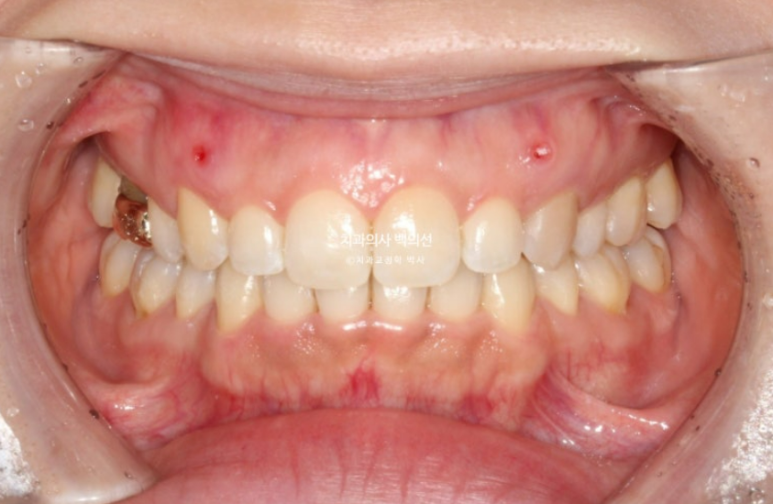

24년 10월부터 25년 4월까지 6개월간 14개의 추가장치를 다 낀 후 모습입니다.

과개교합은 더 개선이 되었고

발치공간은 타이트하게 마무리가 되어 철사유지장치까지 부착했습니다.

앞니가 깊게 물리는 과개교합이 개선되어 비로소 철사유지장치를 붙일 수 있었습니다.

이제 치료 전 후 보겠습니다.

인비절라인 라이트로 치료했고 치료기간은 1년 1개월입니다.

24.03~25.04

과개교합과 중심선의 개선이 보입니다.